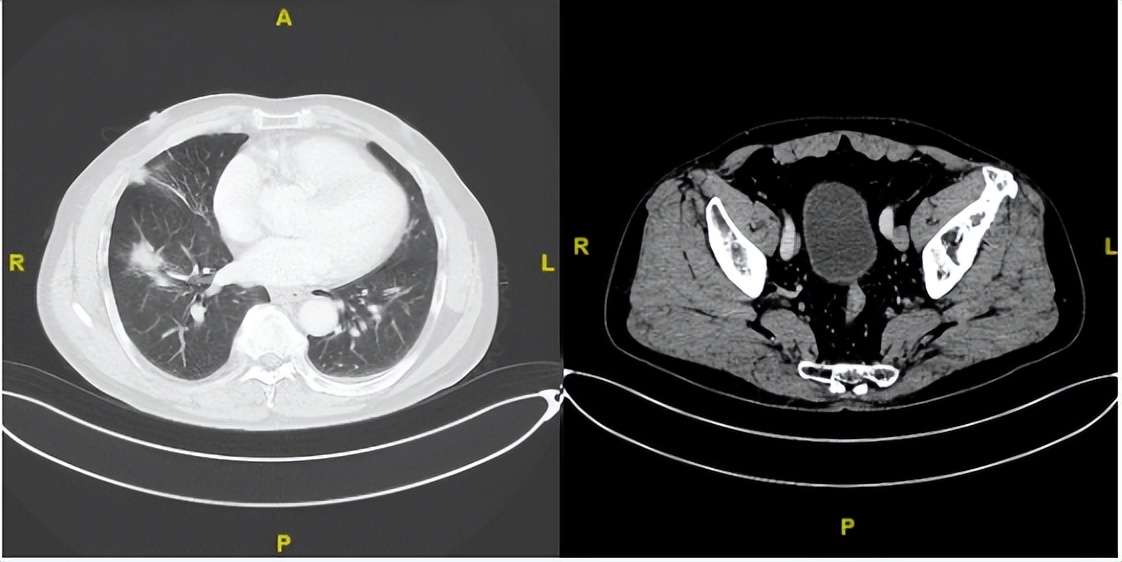

2023年1月31日

△治疗后不同随访时间的胸部及髋关节CT病灶变化